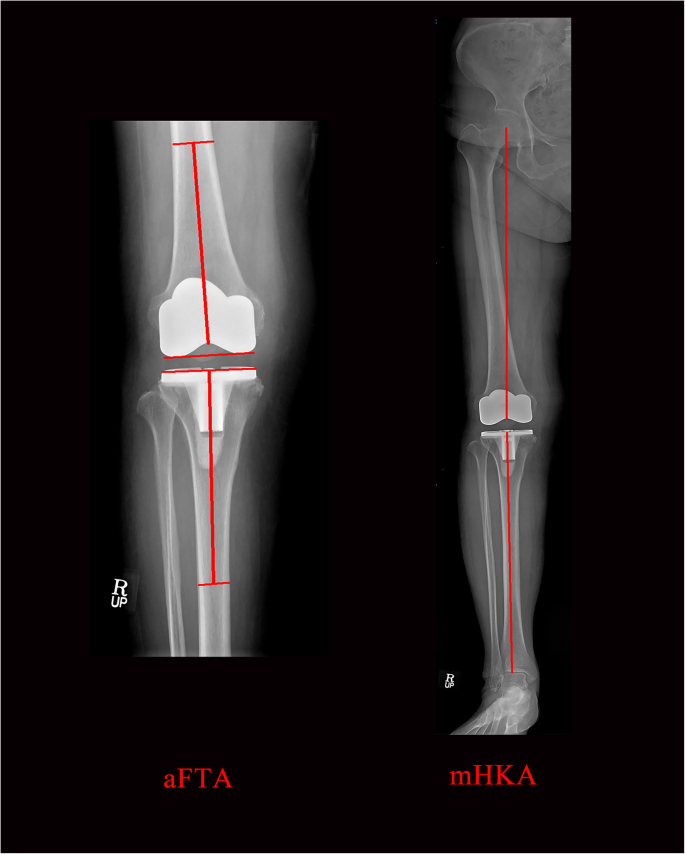

The aFTA was measured from routine 14 × 17 in. weight-bearing AP radiographs, with the patellae facing forward and the legs in full extension, and the mHKA was measured from routine full-length hip–knee–ankle weight-bearing AP radiographs measuring 14 × 51 in. (Fig. 3). Routine weight-bearing AP and lateral knee radiographs (14 × 17 in. cassette) and full-length standing films (14 × 51 in. cassette) were taken at 6 weeks, 3 months, 6 months, 1 year, and every 2–3 years thereafter. Pairs of standing short AP knee radiographs and standing full-length AP radiographs, taken on the same day and in the same position, were evaluated. We measured parameters from radiographs taken within 1.5 years. The alignments on short knee radiographs were classified as neutral (2° ≤ aFTA ≤7°), varus (aFTA < 2°) or valgus (aFTA > 7°) [1, 7, 20, 25]. Postoperative mHKA was expressed as a deviation from 0°, with a positive value for the valgus direction and negative value for the varus direction. The alignments determined from full-length radiographs were also classified as neutral (− 3° ≤ mHKA ≤3°), varus (mHKA < − 3°), or valgus (mHKA > 3°) [2, 8, 13] .

Postoperative short (14 × 17 in. grid cassette) and full-length (14 × 51 in. grid cassette) radiographs showing the measurement of anatomical femorotibial angle (aFTA) and mechanical hip–knee–ankle axis angle (mHKA)

The postoperative aFTA was measured using two lines, the first aligned from the bisection point of the femur, 15 cm above the lowermost portion of the femoral component to the deepest part of the center of the femoral component, and the second from the bisecting point of tibia 15 cm down from the uppermost portion of the tibial component [19]. Postoperative mHKA was made between the two lines, the first aligned from the center of the femoral head to the deepest part of the center of the femoral component, and the second from the midpoint of the inner extension of the tibio-talar joint to the center of the tibial component [14].